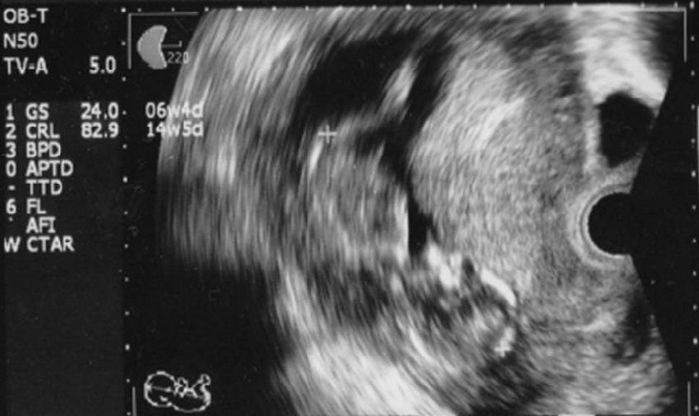

妊娠7週目のエコー写真

頭と体が2頭身に分かれました。